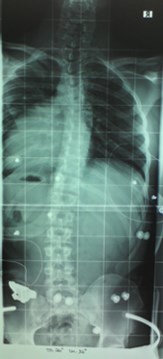

Das Röntgenbild vom November 2011 ist etwa 6 Wochen nach der Kur in Bad Salzungen geschossen worden. Mit 26° thorakal war das mein bester Wert, den ich je hatte. Leider bin ich dann wieder auf das Anfangsniveau von 34° thorakal zurück gefallen, trotz Korsett von cctec und ca. 120 Minuten Schroth-KG pro Woche. Ich muss dazu noch sagen, dass ich von Oktober 2010 bis November 2011 ein Korsett von Rahmouni getragen habe, allerdings nur etwa 8 Stunden am Tag, und die auch nicht am Stück. Das Korsett von cctec habe ich im Schnitt auch nur 8-10 Stunden pro Tag getragen. Aus privaten Gründen trage ich es seit Dezember 2013 nur noch sehr unregelmäßig, manchmal 3 Tage am Stück gar nicht, dann wieder 8 Stunden.